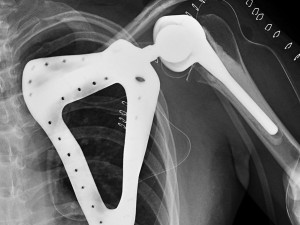

Paceintem svatoananeských lékařů byl teprve třiadvacetiletý mladík, jemuž před rokem odstranili celou lopatku pro nádor. Šlo se o levou končetinu s těžkým funkčním omezením a těžkým kosmetickým defektem. Mladík měl de facto nepoužitelné rameno - jeho pohyblivost byla nulová, protože hlavice pažní kosti se neměla o co opřít. Vzhledem k mladému věku pacienta se tak lékaři rozhodli jít do rozsáhlé implantace ramenního kloubu včetně lopatky.

„Operace trvala 3 hodiny, jednalo se o složitou operaci, navíc v ČR jedinečnou. Bylo nutné vypreparovat zádový sval a jím překrýt umělou lopatku,“ sdělil Tomáš Tomáš. „Náhrada lopatky byla pro pacienta vyrobena na míru, je z titanu a postříbřená z důvodu minimalizace infekce. Je vyrobena pomocí 3D tisku," doplnil.